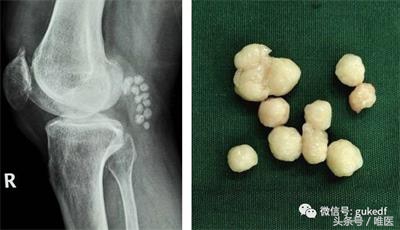

8. 对于关节内软骨剥脱形成游离体,以及半月板撕裂产生卡压、交锁症状的患者能够斟酌膝关节镜下清理游离体(图4)和增生的滑膜组织,或镜下微创缝合损伤撕裂的半月板(图5)。前(后)交叉韧带断裂的可行关节镜下的韧带重建手术(图6)。

图4. 膝关节镜清理游离体